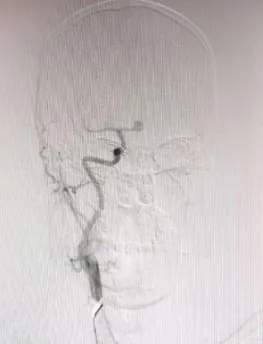

近日,滄州市中心醫(yī)院神經(jīng)血管介入二科為一名突發(fā)蛛網(wǎng)膜下腔出血的患者實(shí)施手術(shù),成功“拆彈”,使患者轉(zhuǎn)危為安。 據(jù)了解,患者陳先生(化名),55歲,在某天夜間突然感到劇烈頭痛,并伴有惡心和嘔吐癥狀,這些癥狀持續(xù)了整整一天。入院1小時(shí)前,他的不適感愈發(fā)明顯,逐漸陷入昏迷狀態(tài),對疼痛刺激已無反應(yīng)。家屬見狀,立即將陳先生送往當(dāng)?shù)蒯t(yī)院就診。醫(yī)生迅速對陳先生進(jìn)行了初步檢查,結(jié)合患者的癥狀和病史懷疑陳先生可能因動(dòng)脈瘤破裂導(dǎo)致蛛網(wǎng)膜下腔出血,情況十分危急。于是,當(dāng)?shù)蒯t(yī)生立即聯(lián)系滄州市中心醫(yī)院神經(jīng)血管介入二科團(tuán)隊(duì),家屬在了解清楚情況后,果斷決定帶患者轉(zhuǎn)往滄州市中心醫(yī)院。 (圖一) 患者到達(dá)滄州市中心醫(yī)院后,神經(jīng)血管介入二科團(tuán)隊(duì)立即展開了緊張的救治工作,迅速為陳先生安排了腦血管造影檢查。造影結(jié)果清晰地顯示:陳先生右側(cè)前交通動(dòng)脈瘤成囊狀,相對寬頸,大小約為7.0*6.9*4.2mm,瘤頂指向上方,形態(tài)不規(guī)則。同時(shí),左側(cè)大腦前動(dòng)脈顯影良好,其余血管未見明顯異常(圖一)。 (圖二) 面對如此緊急和復(fù)雜的病情,神經(jīng)血管介入二科團(tuán)隊(duì)?wèi){借豐富的經(jīng)驗(yàn)和精湛的技術(shù),迅速制定了詳細(xì)的手術(shù)方案——全麻下行顱內(nèi)動(dòng)脈瘤介入栓塞術(shù)。微導(dǎo)管選擇好栓塞部位后,依次送入不同規(guī)格的彈簧圈填充動(dòng)脈瘤。最終造影提示動(dòng)脈瘤的栓塞情況良好(圖二),瘤體周圍的血管沒有狹窄,雙側(cè)大腦前動(dòng)脈的遠(yuǎn)端分支顯影良好。整個(gè)造影過程中,患者的生命體征平穩(wěn)。在團(tuán)隊(duì)的共同努力下,手術(shù)順利進(jìn)行,醫(yī)生成功將陳先生體內(nèi)的“炸彈”——?jiǎng)用}瘤進(jìn)行了妥善處理。患者回到病房后,予心電監(jiān)護(hù)和吸氧,給予鎮(zhèn)靜、預(yù)防抽搐、緩解血管痙攣、補(bǔ)充血容量和抑酸等治療。患者恢復(fù)期間病情逐漸好轉(zhuǎn),順利出院。 什么是顱內(nèi)動(dòng)脈瘤? 顱內(nèi)動(dòng)脈壁局限性、病理性膨起,普遍存在于全球成年人群中。顱內(nèi)動(dòng)脈瘤破裂是導(dǎo)致自發(fā)性蛛網(wǎng)膜下腔出血的首位病因,且多發(fā)生在55~65歲的人群中。盡管不同地區(qū)的死亡率有所下降,但大多數(shù)患者仍遺留有明顯的神經(jīng)功能障礙,這給家庭和社會(huì)造成了沉重的負(fù)擔(dān),嚴(yán)重影響了患者的生活質(zhì)量。因此,顱內(nèi)動(dòng)脈瘤是當(dāng)前嚴(yán)重影響到世界人民生命安全的疾病。隨著醫(yī)學(xué)器械技術(shù)的發(fā)展,動(dòng)脈瘤栓塞介入術(shù)、血流導(dǎo)向裝置植入術(shù)、動(dòng)脈瘤夾閉術(shù)等技術(shù)日趨成熟。 姜紅升主任攜領(lǐng)神經(jīng)血管介入二科團(tuán)隊(duì)提醒您:顱內(nèi)動(dòng)脈瘤是腦中的“定時(shí)炸彈”,動(dòng)脈瘤破裂會(huì)導(dǎo)致蛛網(wǎng)膜下腔出血,致殘率高、死亡率高。其主要癥狀為劇烈頭痛,如突發(fā)難以忍受的頭痛癥狀,不容小覷,應(yīng)及時(shí)到醫(yī)院進(jìn)行診治。未出現(xiàn)動(dòng)脈瘤破裂的患者,應(yīng)及時(shí)控制高血壓、糖尿病、高血脂癥、抽煙、酗酒等高風(fēng)險(xiǎn)因素,并及早根據(jù)個(gè)人動(dòng)脈瘤特征選擇合適的治療方式。 神經(jīng)血管介入二科 國家臨床重點(diǎn)??苿?chuàng)建單位,河北省臨床重點(diǎn)建設(shè)??疲瑴嬷菔信R床重點(diǎn)??疲壳皳碛嗅t(yī)護(hù)人員20人、醫(yī)生6人,護(hù)士14人,其中醫(yī)學(xué)博士1人,碩士研究生導(dǎo)師1人,副主任醫(yī)師2人,主治醫(yī)師1人,住院醫(yī)師3人;主管護(hù)師3人,主持科研項(xiàng)目3項(xiàng),榮獲河北省衛(wèi)健委二等獎(jiǎng)1項(xiàng);近三年內(nèi)發(fā)表SCI論文數(shù)篇,其中一篇發(fā)表于中科院分區(qū)1區(qū)雜志。主要診療范圍:腦血管病的外科手術(shù)與介入治療。我科與北京天壇醫(yī)院、宣武醫(yī)院、天津醫(yī)科大學(xué)總醫(yī)院、天津市環(huán)湖醫(yī)院、河北省醫(yī)科大學(xué)第二醫(yī)院、山東大學(xué)齊魯醫(yī)院等長期保持密切的的友好合作關(guān)系,在顱內(nèi)動(dòng)脈瘤、頸動(dòng)脈狹窄等疾病診療方面,神經(jīng)血管介入二科基于疾病特點(diǎn)以及患者具體情況不同,個(gè)體化的為患者制訂適合的手術(shù)方案;我們科室的發(fā)展理念:以患者的醫(yī)療安全為重中之重、嚴(yán)格把控醫(yī)療質(zhì)量、業(yè)務(wù)水平精益求精、通過熱情誠懇的服務(wù)理念,不忘初心、以德立科,在患者朋友們和醫(yī)院內(nèi)外樹立良好的口碑。 科室診療范圍: 1.蛛網(wǎng)膜下腔出血、顱內(nèi)動(dòng)脈瘤開顱夾閉術(shù)、顱內(nèi)動(dòng)脈瘤介入栓塞術(shù)、血流導(dǎo)向裝置植入術(shù)、瘤內(nèi)擾流裝置植入術(shù)等; 2. 腦血管畸形、硬腦膜動(dòng)靜脈瘺的外科手術(shù)切除與介入栓塞術(shù); 3. 顱內(nèi)外血管狹窄、煙霧病等導(dǎo)致的腦梗死、短暫性腦缺血發(fā)作等,頸動(dòng)脈、椎動(dòng)脈、鎖骨下動(dòng)脈支架及顱內(nèi)動(dòng)脈支架植入術(shù)、頸動(dòng)脈內(nèi)膜剝脫術(shù)、顱內(nèi)外血管搭橋術(shù); 4. 急性腦梗塞動(dòng)脈溶栓、取栓術(shù); 5. 靜脈竇血栓形成溶栓、取栓術(shù),良性顱內(nèi)壓增高綜合征,靜脈竇支架置入術(shù)、巖下竇采血輔助診斷垂體瘤等; 6. 慢性頸動(dòng)脈閉塞再通術(shù)、腦血管畸形介入栓塞+外科手術(shù)切除等、顱內(nèi)高血運(yùn)腫瘤術(shù)前供血?jiǎng)用}栓塞等復(fù)合手術(shù); 7. 脊髓血管造影,硬脊膜動(dòng)靜脈瘺栓塞術(shù); 8. 神經(jīng)危重癥的救治。 門診地址:滄州市中心醫(yī)院腦科院區(qū)北2樓1診室 病區(qū)地址:滄州市中心醫(yī)院腦科院區(qū)北6樓 科室電話:0317-2179505 姜紅升 神經(jīng)血管介入二科副主任(主持工作),黨支部書記,醫(yī)學(xué)博士,碩士研究生導(dǎo)師,副主任醫(yī)師,畢業(yè)于天津醫(yī)科大學(xué)神經(jīng)外科專業(yè),先后于北京天壇醫(yī)院、復(fù)旦大學(xué)華山醫(yī)院、天津醫(yī)科大學(xué)總醫(yī)院、山東大學(xué)齊魯醫(yī)院等學(xué)習(xí)進(jìn)修,主要擅長腦血管疾病的外科手術(shù)及介入治療。主持科研項(xiàng)目多項(xiàng),榮獲河北省衛(wèi)健委二等獎(jiǎng)一項(xiàng)。 專業(yè)擅長:腦動(dòng)脈瘤、血管狹窄、動(dòng)靜脈畸形、煙霧病等腦血管病的手術(shù)及介入治療。